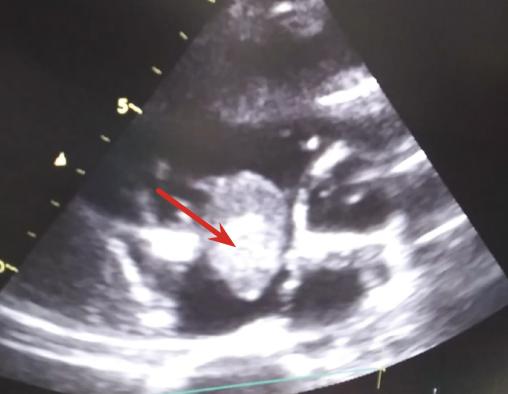

Un angioscanner thoracique objective une embolie pulmonaire bilatérale (fig. 1 ) et une échocardiographie transthoracique montre une masse d’échogénicité hétérogène polylobée mobile mesurant 30 mm, au niveau de l’oreillette droite attachée au septum interatrial (fig. 2 ). L’examen histologique confirme qu’il s’agit d’un thrombus (fig. 3 ). Face à ces résultats, l’indication chirurgicale est posée. Le patient est mis sous traitement anticoagulant, corticothérapie générale et immunosuppresseur.

L’échographie cardiaque permet de poser le diagnostic ; le myxome et la fibrose endomyocardique étant les diagnostics différentiels. L’angioscanner thoracique, voire l’imagerie par résonance magnétique cardiaque, peuvent aussi contribuer au diagnostic.1